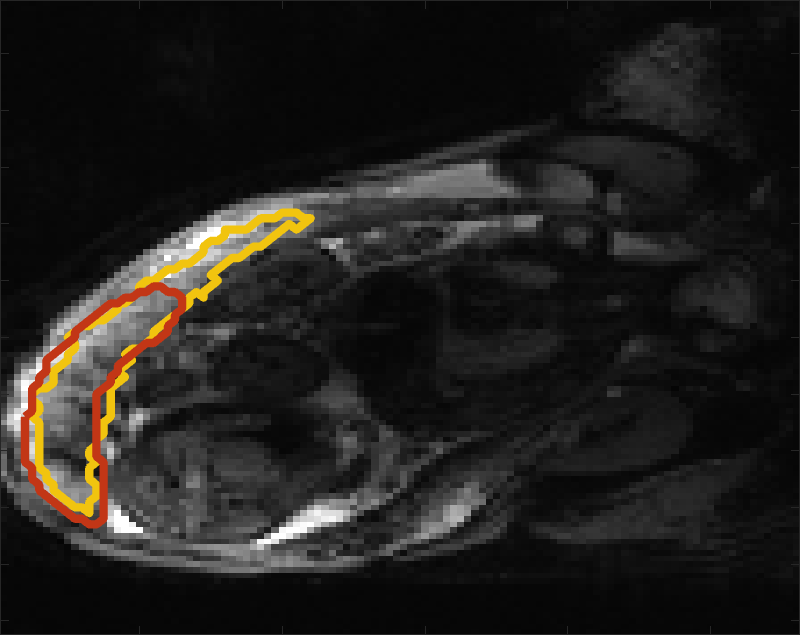

Fig 3 compares the predicted label maps with ground truth on subjects with increasing Dice scores using the BW-CE model. The model accurately identifies the location of the placenta, but in the worst cases misses boundary details.